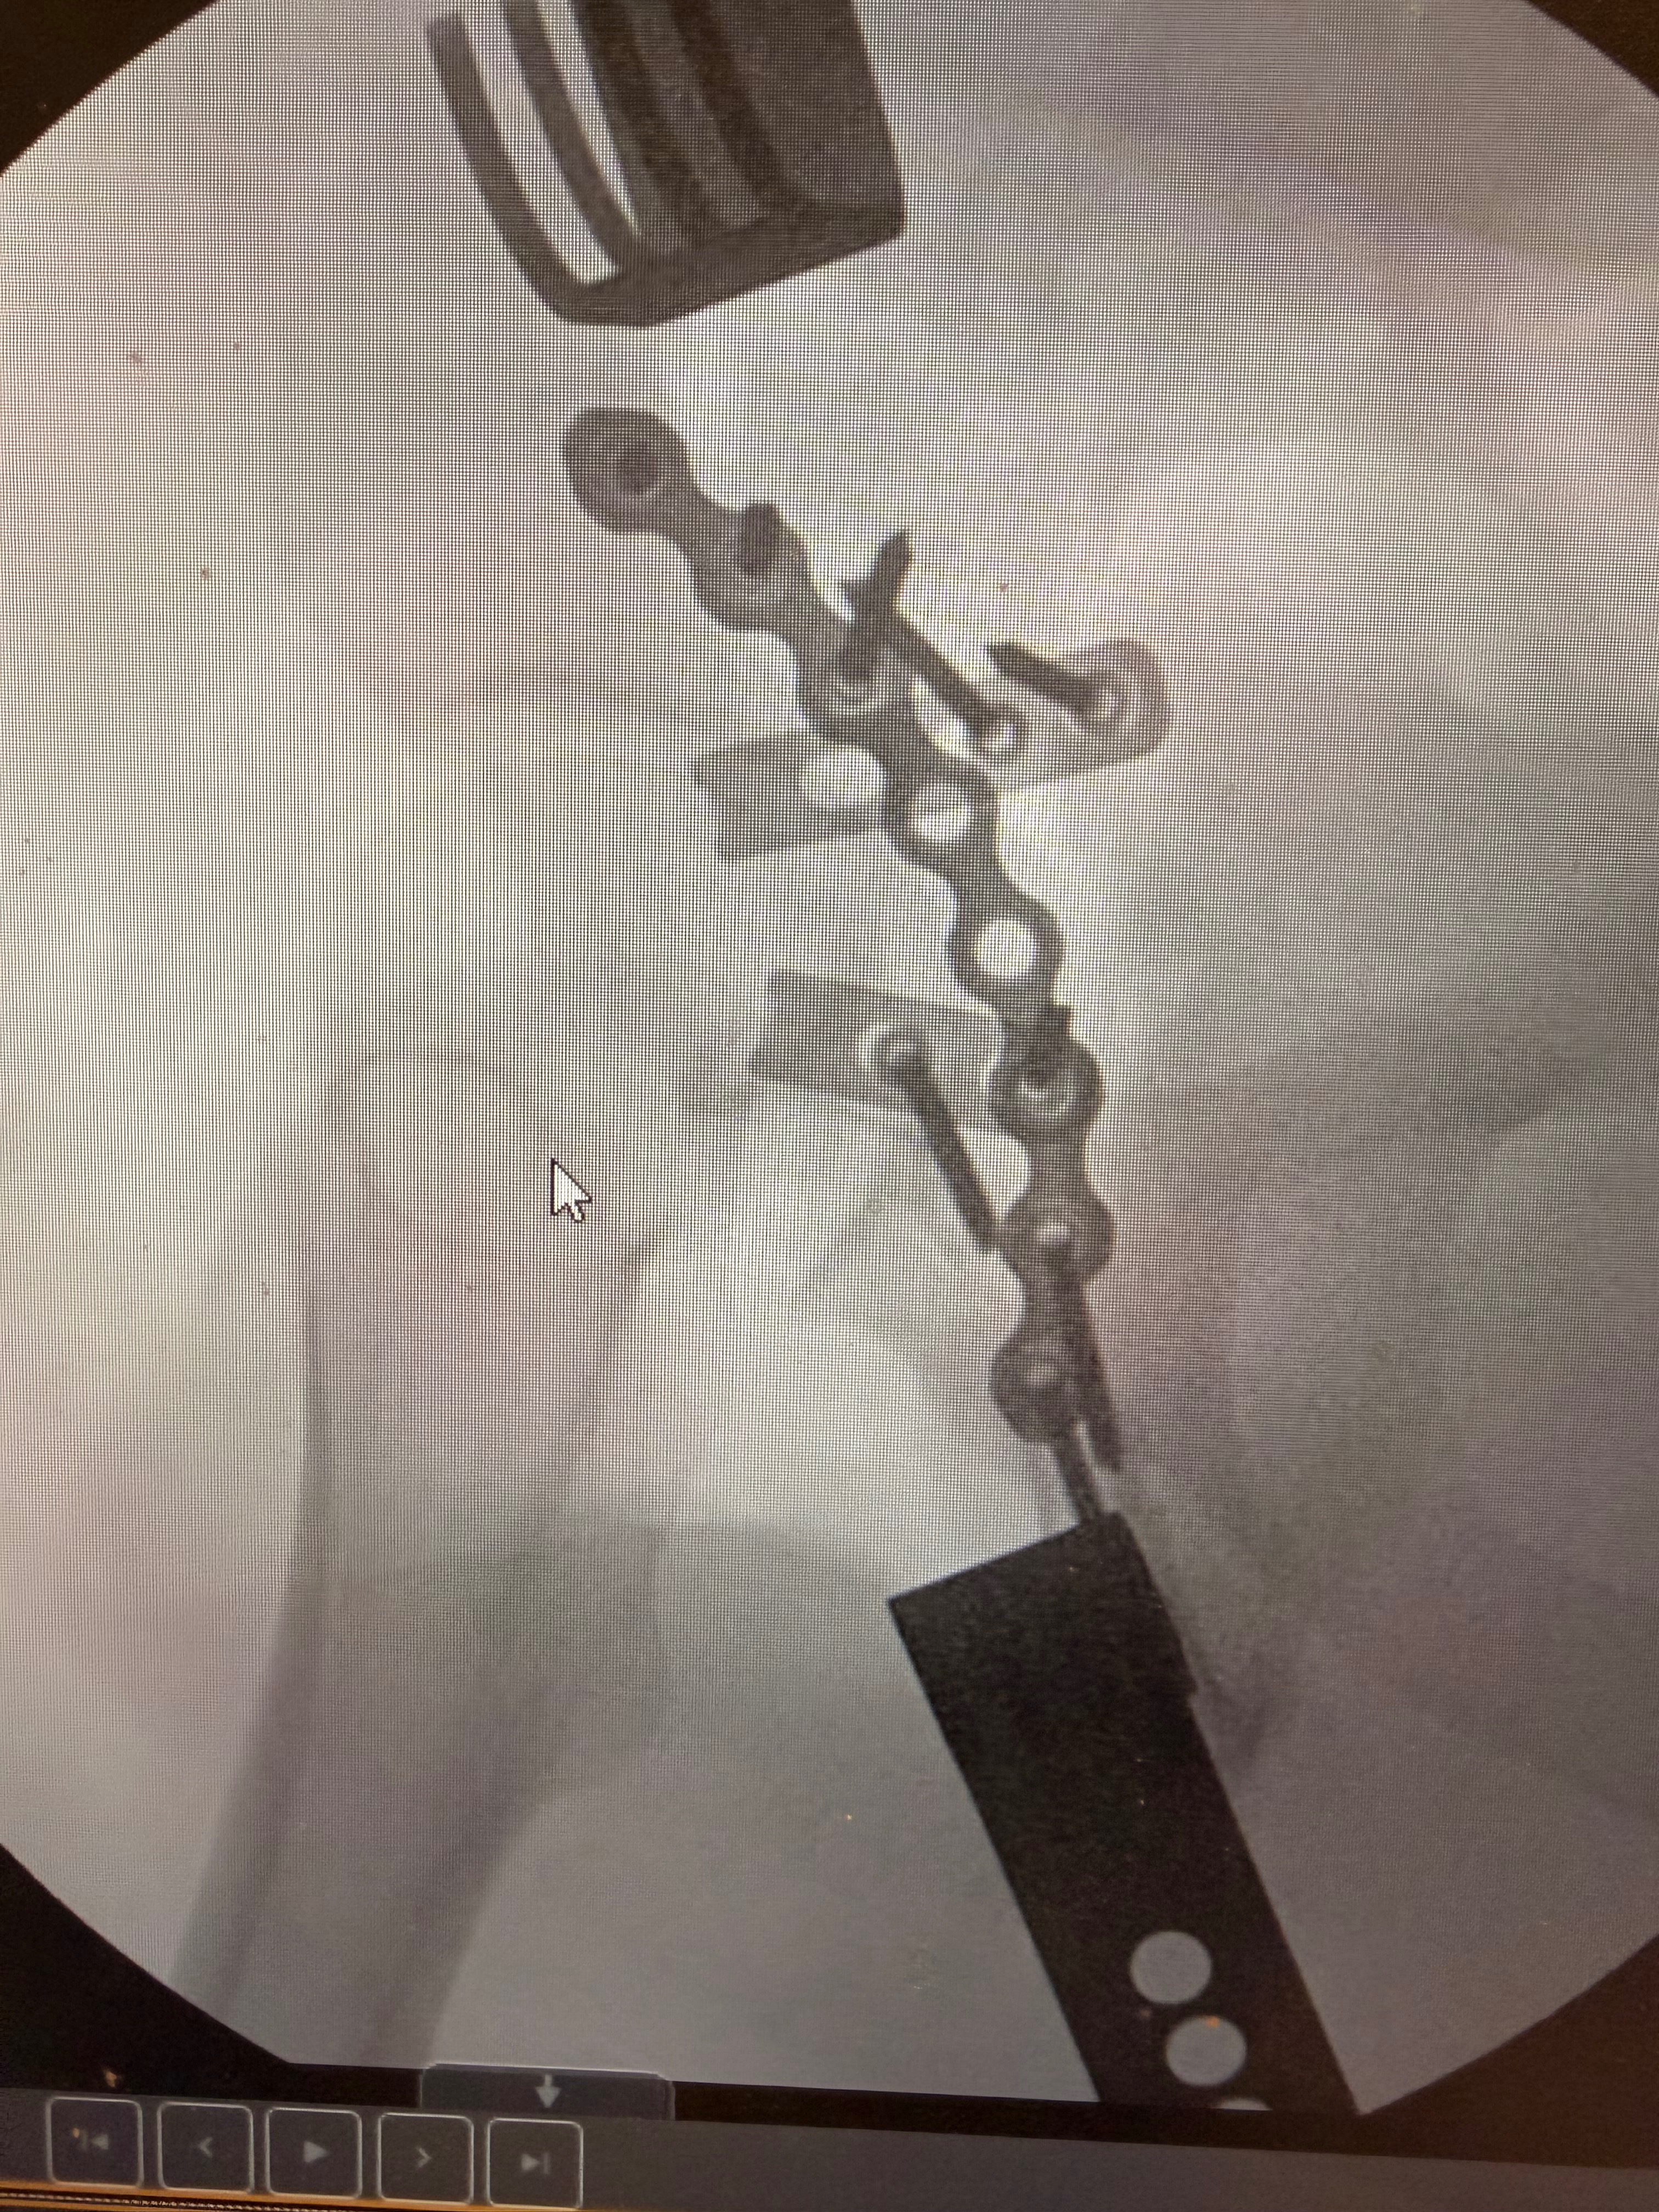

Recently, while training for his upcoming Freestyle Mania tour with Monster Jam, Billy suffered a devastating crash on his home setup. He shattered and dislocated his left hip, fractured his pelvis, and severed his sciatic nerve, leaving him with no mobility in his left foot. The road to recovery is long—doctors estimate 8 to 12 months—and during this time, Billy is unable to work. With no income, he’s facing mounting medical bills and the daily expenses of supporting Willow.